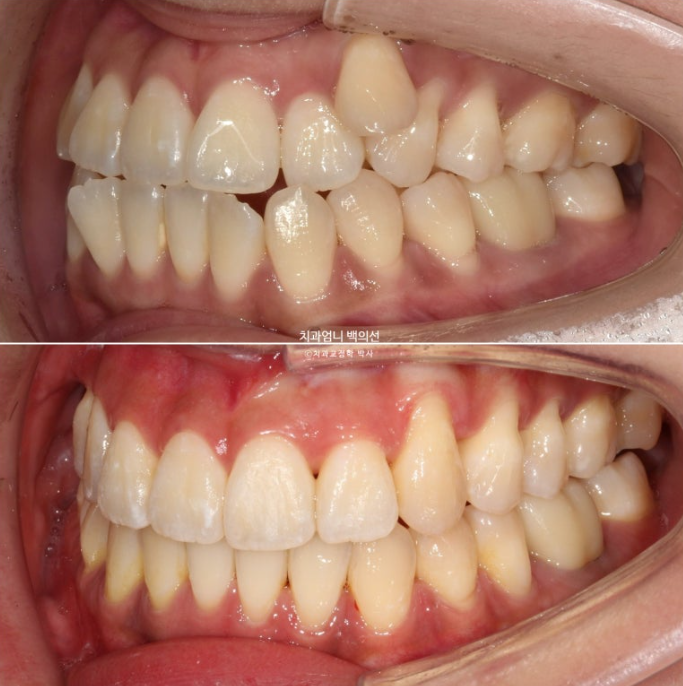

왼쪽 송곳니 하나가 완전히 배열에서 벗어나 있습니다.

덧니가 있으면 덧니쪽으로 중심선이 쏠리기 마련입니다.

위 앞니 중심선이 덧니쪽으로 틀어져 있는 것이 보입니다.

23.09

송곳니가 덧니가 제자리로 들어올 공간이 단 1mm도 없습니다.

심한 덧니입니다.

앞니는 윗니가 아랫니를 덮지 못하고 거꾸로 물리는 반대교합과 절단교합이 보입니다.

이 경우 입을 다물때 아랫입술이 나와보이고 입매가 부자연스럽습니다.

덧니는 제자리를 찾았고 아직 중심선 불일치가 보입니다.

24.11

덧니가 해결되었으니 큰 공사는 끝났네요.